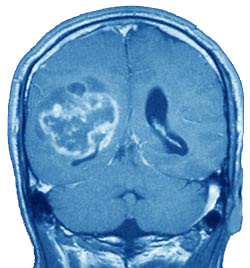

Información: Glioblastoma multiforme. Representa el 25% de todos los tumores cerebrales, el 55% de los tumores del grupo glioma, el 90% de los gliomas de los hemisferios cerebrales del adulto. La punta de incidencia es la edad media de la vida. Hombres doble que mujeres.

Se trata de un tumor altamente maligno muy infiltrante que puede alcanzar un enorme tamaño antes de que llame la atención médica. Puede extenderse hasta la superficie meníngea o pared ventricular. Las células malignas trasportadas por el LCR, pueden formar focos distales en las raices espinales o causar una amplia gliomatosis meníngea. Las metástasis extraneurales son muy raras generalmente afectan al hueso y ganglios lenfáticos después de la craneotomía. Cerca del 50% son bilaterales o ocupan más de un lóbulo o hemisferio. Entre el 3 y 6% son multicéntricos.

El tumor tiene una apariencia variada, siendo gris moteado, naranja o marrón dependiendo del grado de necrosis y la presencia de hemorragia, reciente o antigua. Es altamente vascular y en una arteriografía se puede observar una red de vasos anormales que dan lugar a confusión con un hemangioma y desplazamiento de los vasos normales como resultado del efecto de masa. Alguna porción del ventrículo lateral se encuentra desplazado con frecuencia, tanto el ventrículo lateral como el tercero puede ser desplazado contralateralemnte, rasgos que se demuestran con la TAC.

Los rasgos histológicos característicos son una gran celularidad con pleomorfismo e hipercromatismo de los núcleos; astrocitos identificables con fibrillas en combinación con astroblastos en muchos casos, células tumorales gigantes y células con mitosis; hiperplasia de las células endoteliales de los vasos pequeños y necrosis,hemorragia y trombosis de los vasos. Originalmente se pensó como derivado de células embrionarias primitivass, se piensa ahora que deriva de anaplasia de astrocitos maduros. Kernohan sugiere que el término glioblastoma sea sustituido por el de astrocitoma maligno,grado 3 o 4..Normalmente los términos más empleados son glioblastoma multiforme y astrocitoma anaplásico, estos términos normalmente corresponden a los astrocitomas grados 3 y 4. los dos tumores difieren en la edad de comienzo y respuesta al tratamiento. La edad media del pacientes con glioblastoma multiforme es de 56 años y con astrocitoma anaplásico de 46. En las series amplias recientes, la supervivencia postoperatoria a los 18 meses fue del 15% en los pacientes con glioblastoma y del 62% en pacientes con astrocitoma anaplásico.